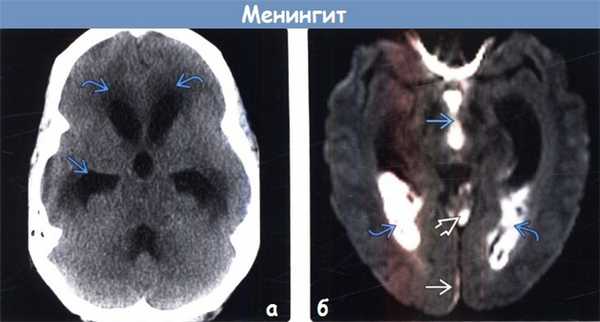

(а) Бесконтрастная КТ: у пациента с пневмококковым менингитом определяется сообщающаяся гидроцефалия с понижением плотности мозговой ткани в перивентрикулярных отделах, что обусловлено перивентрикулярным интерстициальным отеком.

(б) МРТ, ДВИ, аксиальный срез: у этого же пациента наблюдаются осложнения менингита. Ограничение диффузии наблюдается в III желудочке и затылочных рогах боковых желудочков, что обусловлено вентрикулитом. В парасаггитальном отделе правой затылочной области присутствует непротяженная субдуральная эмпиема. Обратите внимание на повышение интенсивности сигнала на ДВИ, обусловленное экссудатом в верхней мозжечковой цистерне.